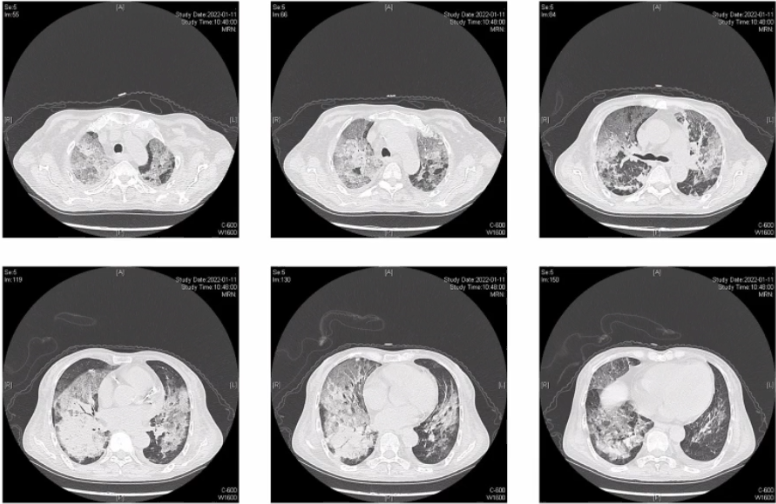

入院前1天阵发性气促,伴发热,体温38.5°C,血氧饱和度88%,夜间尚可平卧休息。全身躯干、双下肢浮肿。查血气分析(HFNC,FiO0.61,流速60 L/min):pH 7.527,PaCO2 30.6 mmHg,PaO2 56.7 mmHg,Lac 3.3 mmol/L。血常规:WBC 6.9×109/L,NEU% 93.6%,HGB 92 g/L,PLT 140×109/L。胸部CT:双肺渗出、实变改变(图1),肺动脉增宽,心包少量积液,合并心源性肺水肿可能。治疗方面予美罗培南0.5 g静滴q12h抗感染(2022年1月11-12日),味塞米利尿等治疗,气促无缓解,伴严重低氧血症,监测SpO2波动于80%~90%之间。现为进一步诊治,就诊于我科,拟“重症肺炎,Ⅰ型呼吸衰竭”收住入院。

图片

图1  患者外院胸部CT